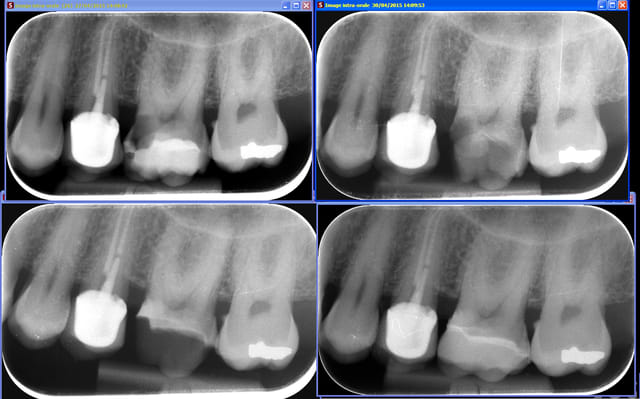

Tiens, un cas juxta-pulpaire fait il y a quelques mois : biodentine, remontée de marge, IDS et onlay Emax. La dent est vivante et asymptomatique...

> Tiens, un cas juxta-pulpaire fait il y a quelques mois : biodentine, remontée de

> marge, IDS et onlay Emax. La dent est vivante et asymptomatique...

Après faut faire le détartrage aussi :P (mésiale 27 ^^)